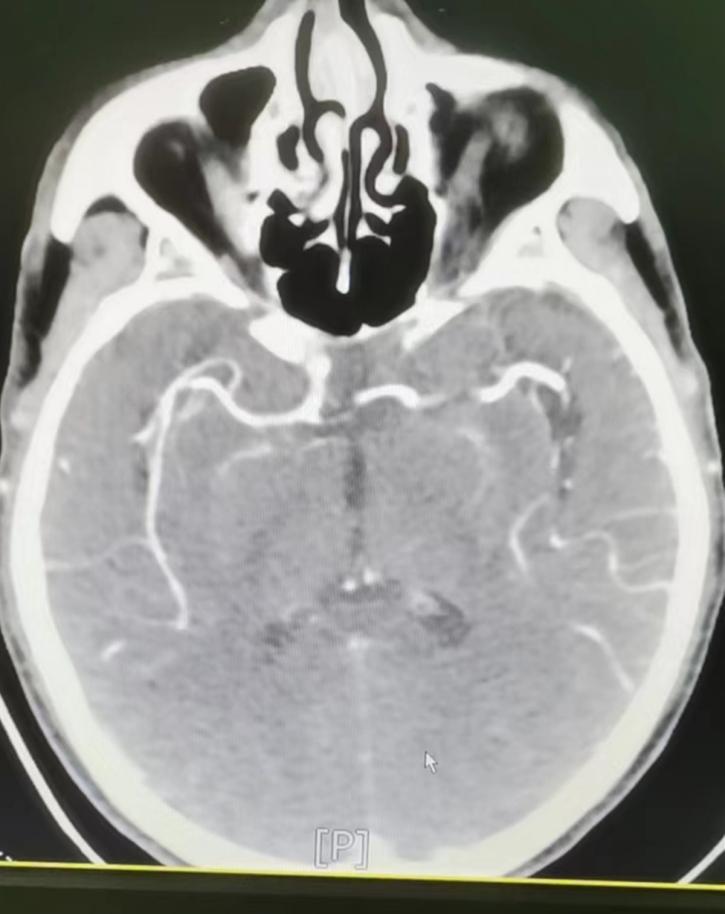

9月3日,商洛市某隔离点工作人员刘某突发左侧肢体无力收住我院援商洛医疗队负责组建、运行的商洛黄码医院。医疗队员神经内科杜赟主治医师诊查后考虑患者病情进行性加重,当地医疗条件有限,应尽快上转。医疗队领导协调各方资源,于当天22时55分,在杜赟主治医师与刘轲寒护士护送下转入我院,发热单元开通绿色通道,神经内科、影像科多学科协作,顺利完成大血管评估并给出精准治疗方案。第二天患者病情明显好转,现已转入神经内科普通病房进一步治疗。

图4 CTA显示右侧大脑中动脉通畅